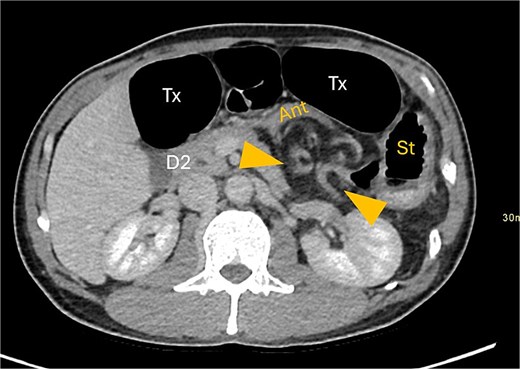

A contrast-enhanced computed tomography (CT) scan of the abdomen and pelvis demonstrated a large bowel obstruction with a transition point at the distal transverse colon with swirling of the mesentery. Downstream large bowel was collapsed. Upstream dilatation included the terminal ileum suggested an incompetent ileo-caecal valve. The gastric antrum was also involved in the internal hernia, resulting in gastric outlet obstruction. See Figs 1–5.

Gastric outflow obstruction of stomach (st) from compression of antrum (ant) by herniated transverse colon. Hernia between arrows.

Posterior displacement of the duodenum (D4) due to herniated transverse colon.